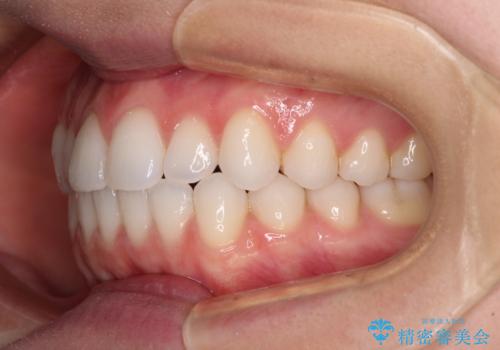

上下前歯が接触しない オープンバイトをインビザラインで改善

- 前歯の上下スペースによる食べにくさを気にして来院された患者様です。

インビザラインにより上下の前歯の隙間を閉じていくこととしました。

上下の奥歯を圧下させるようにすることで、前歯を接触させるように計画しました。

上下の隙間に舌が入り込むことがオープンバイトの原因であったため、舌の筋肉のトレーニングも並行して行い、後戻りの抑制を図りました。